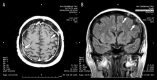

BACKGROUND Meningeal carcinomatosis is a rare complication in breast cancer patients. At present, there are no defined guidelines for its management. The efficacy of systemic treatment seems to depend on its ability to cross the blood-brain-barrier and its interaction with tumor vasculature. Metronomic chemotherapy is a known modality of drug administration able to inhibit tumor angiogenesis. CASE REPORT We present a case of symptomatic leptomeningeal carcinomatosis from breast cancer successfully treated with capecitabine. Based on the hypothesis that angiogenesis contributes to neoplastic meningitis, the patient was treated with a metronomic schedule that provided long-term clinical benefit with a very low toxicity profile. CONCLUSIONS To assess the real impact of metronomic chemotherapy in patients with meninges involvement, a phase II study will be starting soon in our institution. A review of the literature concerning the management of meningeal carcinomatosis is also presented.